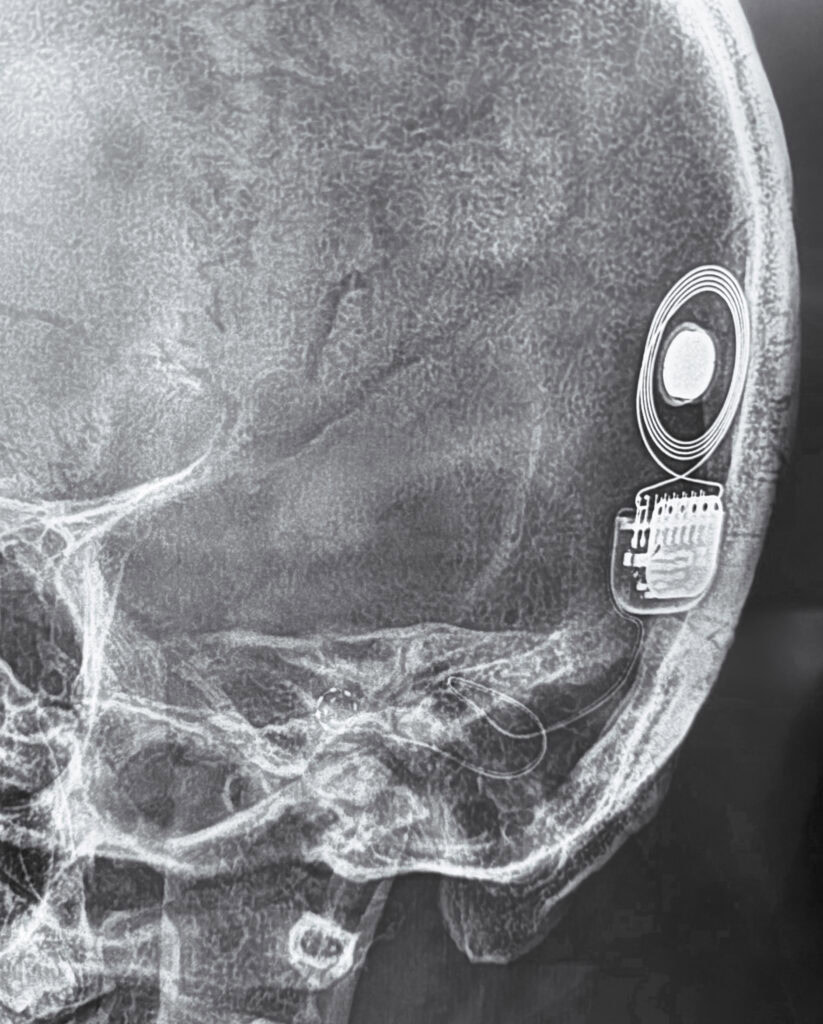

Below is a picture of post-op XRay showing how the implant is placed inside my head. Notice the looped wire that ends in a spiral inside the cochlea. 12 electrodes can be counted inside the spiral.